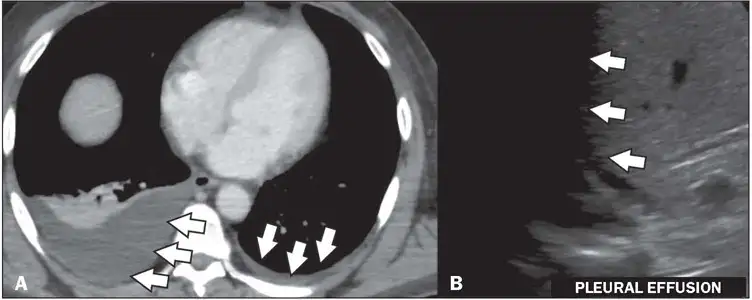

当发热开始消退时,疾病进入关键的"危险期",通常持续24至48小时。这是最危险的时刻。在少数患者中,血管内皮细胞开始渗漏,血浆从血管中渗出到周围组织。患者可能出现严重的腹痛、持续呕吐、牙龈出血、皮肤出现瘀点或瘀斑。如果血管渗漏严重,大量体液在胸腔和腹腔积聚,有效循环血量急剧下降,患者就会进入休克状态。

登革热休克综合征(Dengue Shock Syndrome,DSS)是登革热最致命的并发症。患者的血压急剧下降,脉搏微弱,皮肤湿冷,意识模糊。如果不能及时补液,多器官衰竭将在数小时内夺走患者的生命。在未经治疗的情况下,DSS的死亡率可高达20%以上;而及时的正确治疗可以将死亡率降低到1%以下。

血管渗漏的机制至今仍是活跃的研究领域。目前认为,登革热病毒的NS1蛋白起着核心作用。NS1可以激活补体系统,产生炎症介质;它可以诱导巨噬细胞释放大量促炎细胞因子,如白细胞介素-6(IL-6)和白细胞介素-8(IL-8);它还可以直接破坏血管内皮细胞之间的连接,增加血管通透性。此外,抗NS1抗体还可能与血管内皮细胞发生交叉反应,导致自身免疫损伤。

血小板减少是登革热的另一个标志性特征。正常人的血小板计数在每微升15万至45万之间,而重症登革热患者的血小板可以降至每微升2万以下。血小板减少的机制是多方面的:病毒可以直接抑制骨髓中血小板的产生;抗血小板抗体可以加速血小板的破坏;脾脏对血小球的扣押增加。血小板减少会导致出血倾向,从轻微的牙龈出血、鼻衄,到严重的消化道出血、颅内出血。

重症登革热的识别至关重要。世界卫生组织定义的预警信号包括:严重腹痛、持续呕吐、体液蓄积(腹水、胸腔积液)、黏膜出血、嗜睡或烦躁不安、肝脏肿大、红细胞压积升高伴血小板下降。任何出现这些预警信号的患者都应立即住院治疗。影像学检查在重症登革热的诊断和监测中发挥着重要作用。超声检查可以快速发现胆囊壁增厚、腹水、胸腔积液等典型的登革热表现,这些发现对于判断疾病严重程度和指导治疗具有重要价值。